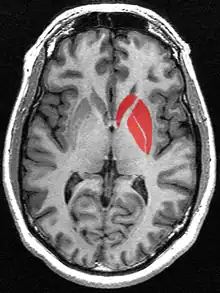

The striatum as seen on MRI. The striatum includes the caudate nucleus and the lentiform nucleus which includes the putamen and the globus pallidus

The striatum in red as seen on MRI. The striatum includes the caudate nucleus (top), and the lentiform nucleus (the putamen (right) and the globus pallidus (lower left))

The striatum is the largest structure of the basal ganglia. The striatum is divided into two subdivisions, a ventral striatum and a dorsal striatum, based upon function and connections. It is also divisible into a matrix and embedded striosomes.